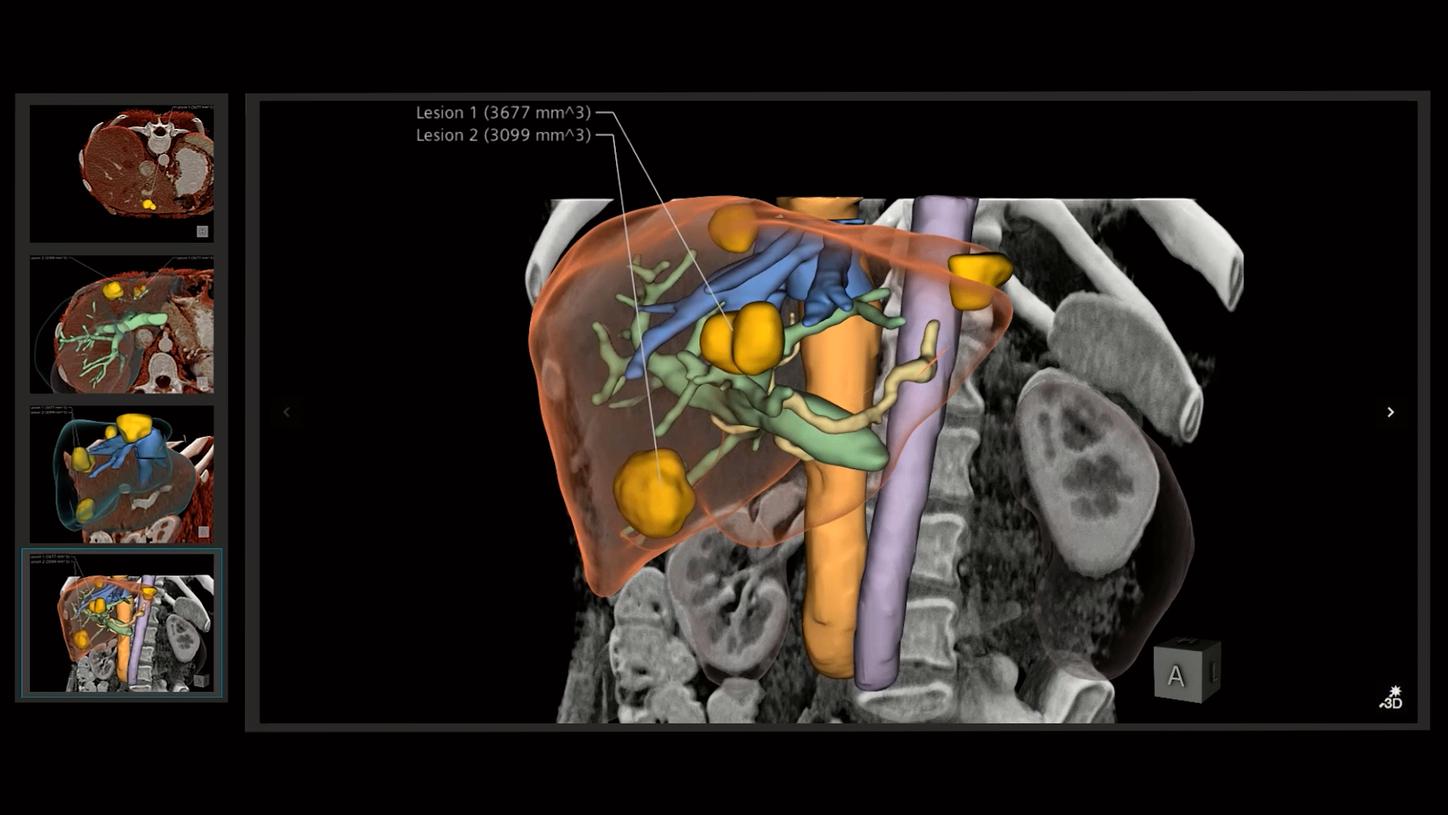

In the area of surgical guidance, for example, they use computer graphics for minimally invasive surgery, such as laparoscopic procedures. “We generate overlays using computer graphics techniques that synthesize patient data, pre-operative data, and planning data, and display it on top of the video feed in such a way that we can help the surgeons do a better job,” Kal explains. “And by using the correct depth visualization techniques, we allow them to see 3D structures in ways they could not before.”

Another field of application is education and training. Here they also use techniques from the movie industry to create photorealistic renderings of patient cases. The idea is to train future doctors and clinicians using actual patient- and disease-specific data. Another field that is a focus of Kal and his colleagues: They want to use 3D image visualization to support dialogue with patients by allowing physicians to communicate information about the disease in a more illustrative way.